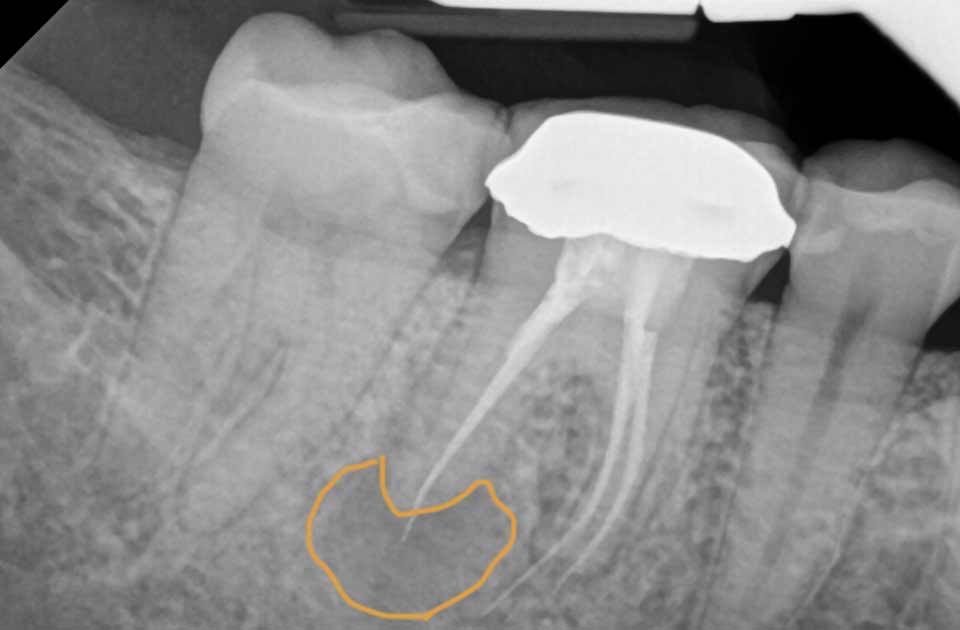

آبسه ها

ممکن است به دلیل انجام ناقص عصب کشی دندان ، آبسه ایجاد شود . آبسه در محل حفره اصلی تشکیل می شود این عارضه می تواند یک مشکل جدی برای سلامتی باشد زیرا توده ای پر از چرک است و می تواند باعث عفونت جدی شود در صورت عدم درمان آبسه می تواند پاره شود و عفونت به سایر قسمت های بدن سرایت کند .

معمولا در درمان کانال ریشه ناحیه عفونی باید به خوبی تمیز و مهر و موم شود اگر کانال ریشه کامل نباشد و مراحل به خوبی انجام نشود باکتری ها دوباره وارد آن قسمت دندان شده و عفونت می کنند عفونت می تواند به سایر نواحی دهان یا استخوان فک سرایت کند و ناتمام ماندن کانال ریشه می تواند بیمار را در معرض خطر مشکلات جدی دندانی و شرایط پزشکی قرار دهد .

یافتن کانال های کوچک یا ریشه های نادیده گرفته شده توسط اشعه ایکس پس از درمان اولیه